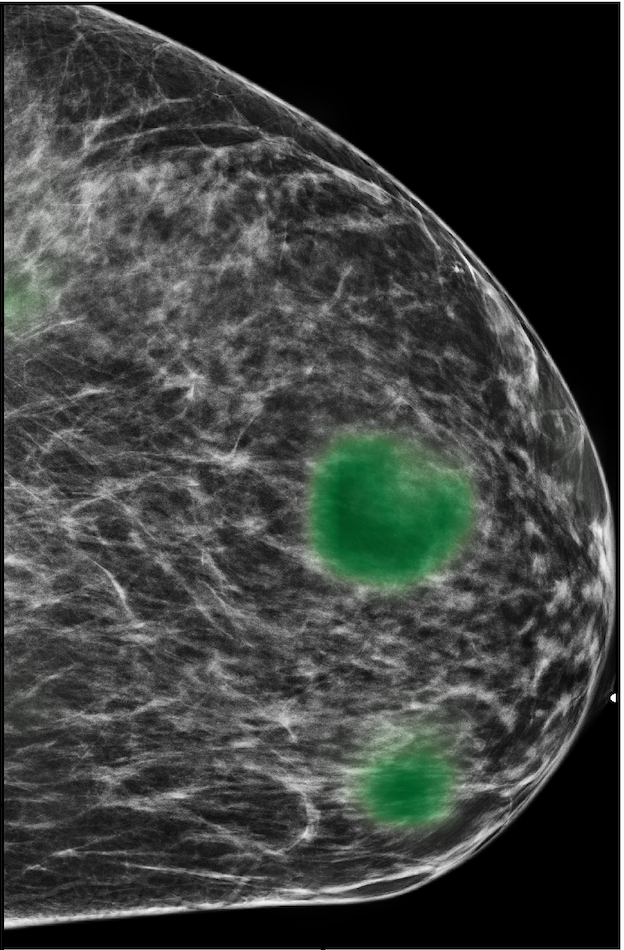

To evaluate the localization performance of GMIC, we select the model with the highest DSC for malignancy localization using the validation set. During inference, we upsample saliency maps using nearest neighbour interpolation to match the resolution of the input image. Our best localization model achieves a mean test DSC of 0.325 (std:0.231) for localization of malignant lesions and 0.240 (std:0.175) for localization of benign lesions. The best localization model achieves an AUC of 0.886/0.78 on classifying malignant/benign lesions. We observe that localization and classification performance are not perfectly correlated. The trade-off between classification and localization has been discussed in the weakly supervised object detection literature [15, 62, 82].

In Figure 7, we visualize saliency maps for four samples selected from the test set. In the first two examples, the saliency maps are highly activated on the annotated lesions, suggesting that our model is able to detect suspicious lesions without pixel-level supervision. Moreover, the attention is highly concentrated on ROI patches that overlap with the annotated lesions. In the third example, the saliency map for benign findings identifies three abnormalities. Although only the top abnormality was escalated for biopsy and hence annotated by radiologists, the radiologist’s report confirms that the two non-biopsied findings have a high probability of benignity and a low probability of malignancy. In the fourth example, we illustrate a case when there is some level of disagreement between our model and the annotation in the dataset. The malignancy saliency map only highlights part of a large malignant lesion with segmental coarse heterogeneous calcifications. This behavior is related to the design of : a fixed pooling threshold cannot be optimal for all sizes of ROI. The impact of is further studied in 3.6. This example also illustrates that while human experts are asked to annotate the entire lesion, CNNs tend to emphasize only the most informative regions. While no benign lesion is present, the benign saliency map still highlights regions similar to that in the malignancy saliency map, but with a lower probability than the malignancy saliency map. In fact, calcifications with this morphology and distribution can also result from benign pathophysiology [42].